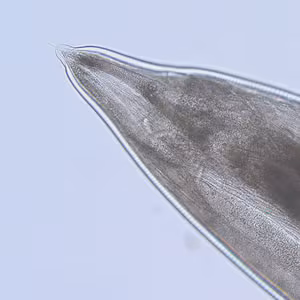

A worm measuring approximately 11 mm in length was sent to CDC for identification by a laboratory in the Southeastern United States. The following images were obtained by placing the worm on a 1″ × 3″ glass slide and gently “floating” a 24 × 30 mm glass coverslip on top of it with water. Figure A shows the anterior end of the worm. Figures B and C (a digital zoom of B) show the posterior end of the worm. All images were captured at 100× magnification. Based on the images, identification at the genus level, as well as determination of whether the worm is male or female, is possible. What is your diagnosis? Based on what criteria?

Figure A